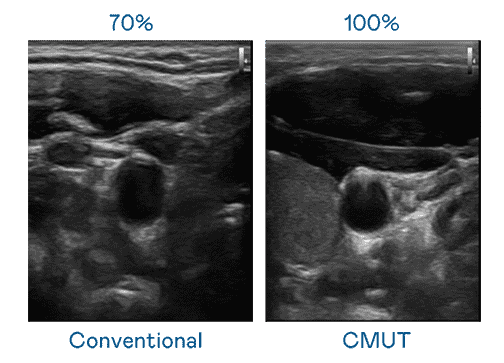

CMUT 技术是一种用电容式微机电元件来产生超音波讯号的技术。。。与传统 PZT 压电式技术相比,,,,CMUT 频宽增加 30%,,更宽频的超音波讯号让影像解析度大幅提升,,,,是实现高影像品质医疗超音波扫描、、、促进精准医疗发展的关键技术。。。

大频宽带来超清晰影像

超音波影像的解析度高低,,,首先取决于探头能发出的讯号频宽。。汇旺支付 CMUT 可提供高清晰的超音波讯号,,,,提供高频宽、、、高灵敏度、、影像纹理细节更高的超音波影像,,,,协助医护人员缩短影像判读时间及利用精准的医疗影像进行诊断。。。。